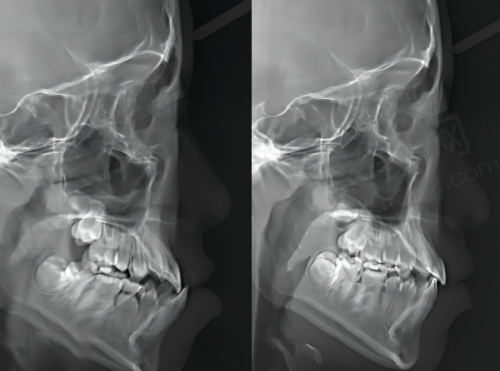

精良的设备对于口腔诊疗至关重要。天津中幸口腔医院拥有数字化口腔CT机、数字化曲面断层全景机、数字化X线机、口腔扫描仪等一系列精良设备。这些设备能够为患者提供精细、效率高、舒适的口腔诊疗服务。比如数字化口腔CT机,它可以清晰地呈现口腔内部的结构,帮助医生更正确地诊断病情。还有口腔扫描仪,能快速获取牙齿的三维模型,为后续的治疗提供严谨的数据。精良的设备不仅提高了诊疗的正确性和效率,也让患者在治疗过程中更加舒适。因此,从设备方面来看,天津中幸口腔医院处于较高的档次。